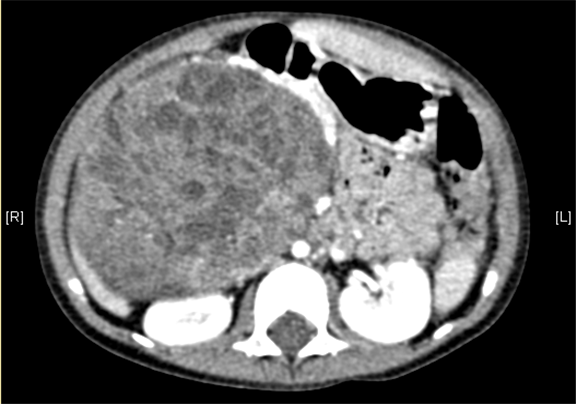

术前CT检查:

静脉期

上腹部增强CT提示肝门处占位性病变,考虑腹膜后肿瘤可能性大,畸胎瘤? AFP 11.38ng/ml

模拟手术操作,自动计算切除肿瘤体积。肝脏体积为459.7ml,肿瘤体积为363.7ml,肿瘤体积为肝脏体积的79.12%,通过比对3-岁正常肝脏体积为248.41±85.99ml,通过术前模拟手术,精准判断切除后剩余肝脏体积能耐受,避免肝衰竭发生。